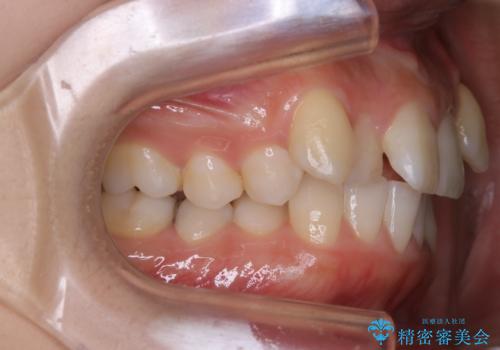

左側のかみ合わせは、歯1本分かみ合わせが前にずれていました。上顎左右の奥歯を2本抜歯しています。

がたつきだけでなく、奥歯の噛み合わせのずれの調整もしっかり行いました。

奥歯のずれの調整は時間がかかりますが、矯正後の歯並びの安定度が向上します。